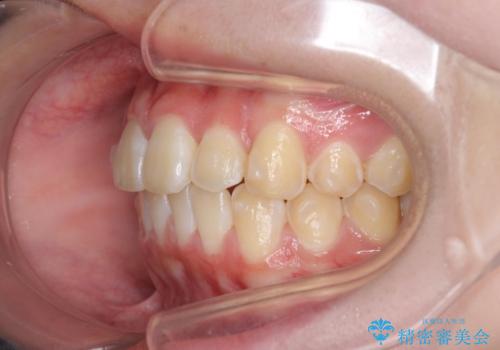

前歯のがたつき気になる。インビザラインモデレート

- 前歯のがたつきが気になるとの事で来院。

マウスピース矯正希望でしたのでインビザラインモデレートで治療を行いました。

がたつきが無くなり満足して頂けました。

矯正が終わった後は保定装置を使用しないと後戻りしてしまうのでしっかりと保定装置を使用する必要があります。